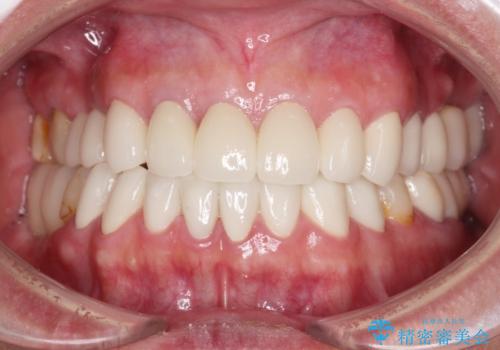

- クラウンを装着したばかりの歯の歯肉が腫れていることを気にして来院された患者様です。

むし歯がとても大きく、歯茎に歯の一部が埋もれてしまっているため、汚れが溜まりやすくなっている状態でした。

根歯の挺出(歯を引っ張り出す部分矯正)、歯周外科処置などを行った後、オールセラミッククラウンにて補綴することとしました。

当初は歯肉が腫れ上がり、大変不快な思いをされていましたが、セラミッククラウン装着後は清掃性が著しく改善し、患者様には大変満足していただきました。